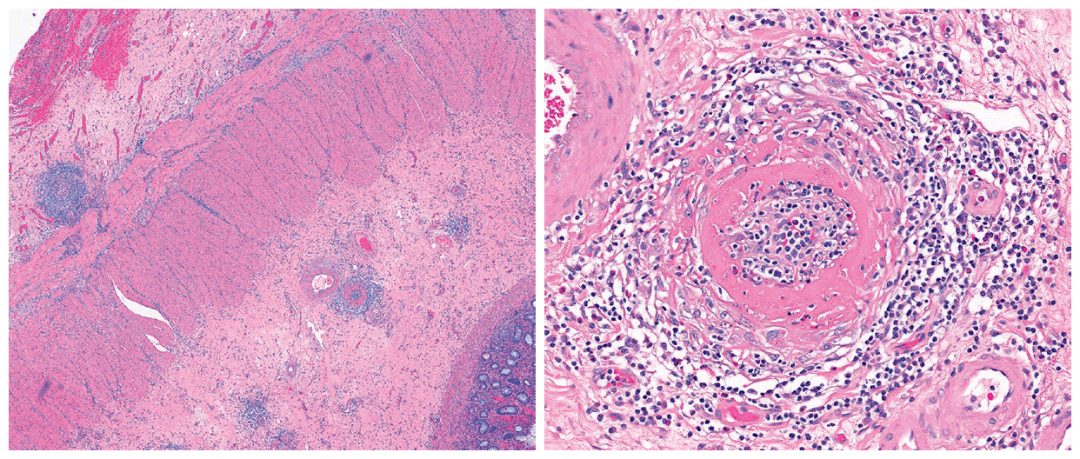

右半结肠切除标本,肠壁全层切片,可见累及小至中等动脉的血管炎

病理切片-动脉粥样硬化 诊断描述:低倍镜下可见血管内膜增厚,向血管

切面一侧为较正常的主动脉,一侧主动脉内膜不规则增厚,纤维组织增生